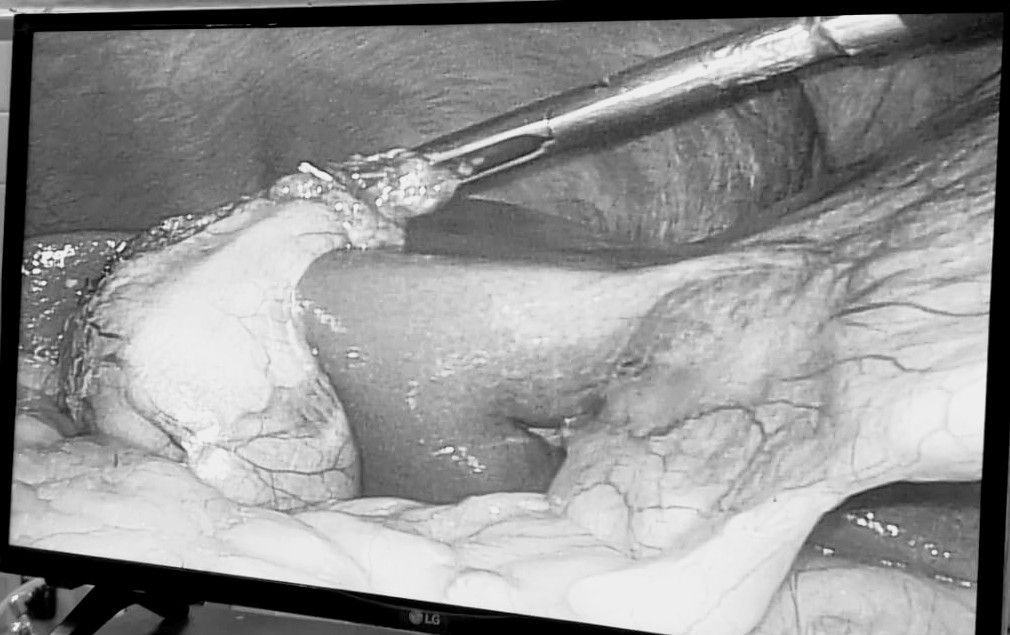

Mi experiencia abarca un espectro diverso, desde apendicitis hasta afecciones de la vesícula biliar, el colon y el recto. Como especialista en Laparoscopia, estoy dedicado a utilizar técnicas avanzadas y soluciones personalizadas para abordar las necesidades únicas de cada paciente.

• Cirugía laparoscópica

• Apendicectomia por laparoscopia